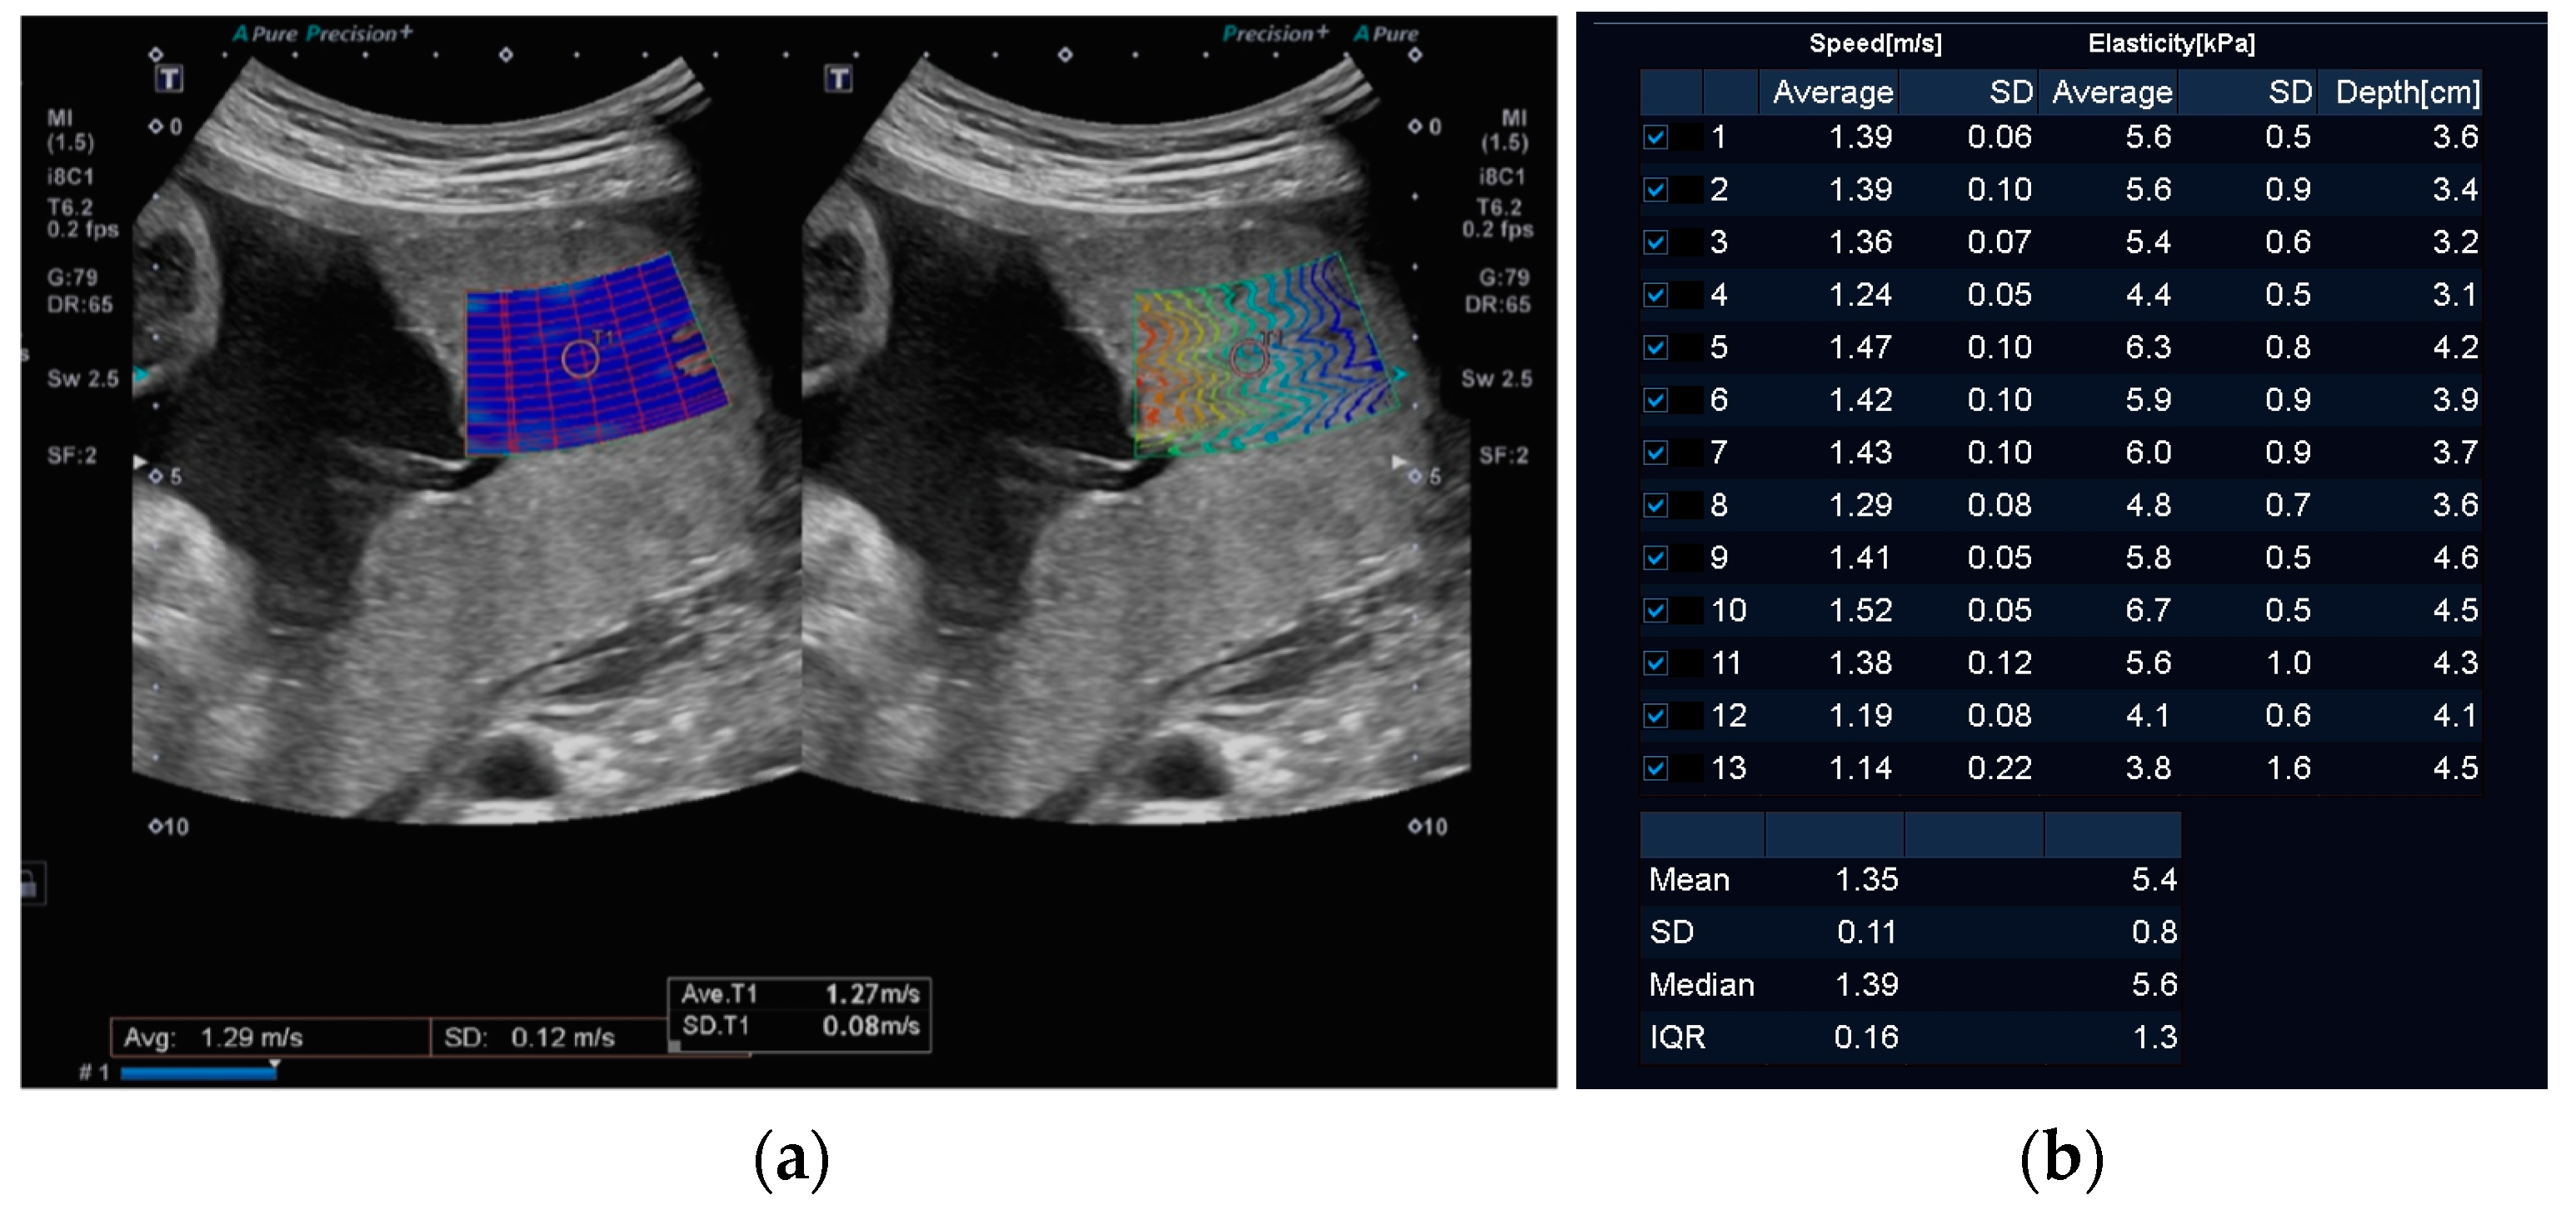

2.2. Equipment and Methods

- Weiher, M.; Richtering, F.G.; Dörffel, Y.; Müller, H.P. Simplification of 2D shear wave elastography by enlarged SWE box and multiple regions of interest in one acquisition. PLoS ONE 2022, 17, e0273769. [Google Scholar] [CrossRef]

- O’Hara, S.; Zelesco, M.; Rocke, K.; Stevenson, G.; Sun, Z. Reliability Indicators for 2-Dimensional Shear Wave Elastography. J. Ultrasound Med. 2019, 38, 3065–3071. [Google Scholar] [CrossRef] [PubMed]

- Edwards, C.; Cavanagh, E.; Kumar, S.; Clifton, V.; Fontanarosa, D. Intra-system reliability assessment of 2-dimensional shear wave elastography. Appl. Sci. 2021, 11, 2992. [Google Scholar] [CrossRef]